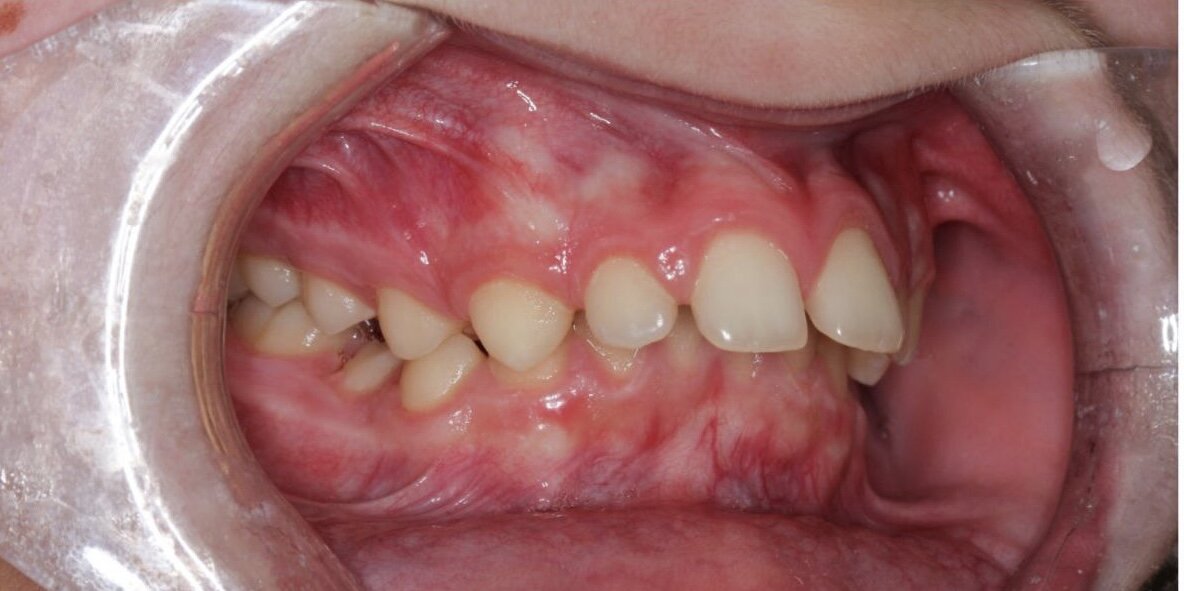

Дистальный прикус в подростковом возрасте. Результат ортодонтического лечения без хирургического вмешательства.

Изначальная ситуация в полости рта достаточно сложная:

• Дистальный прикус

• Глубокая окклюзия

• В профиль видно, что губы не смыкаются, резцы торчат и сильно отклонены вперед.

Чем это плохо помимо эстетики? Глубокий прикус ведет к сколам зубов и травматизациям десны.

При несмыкании губ они постоянно обветрены и травмированы резцами.